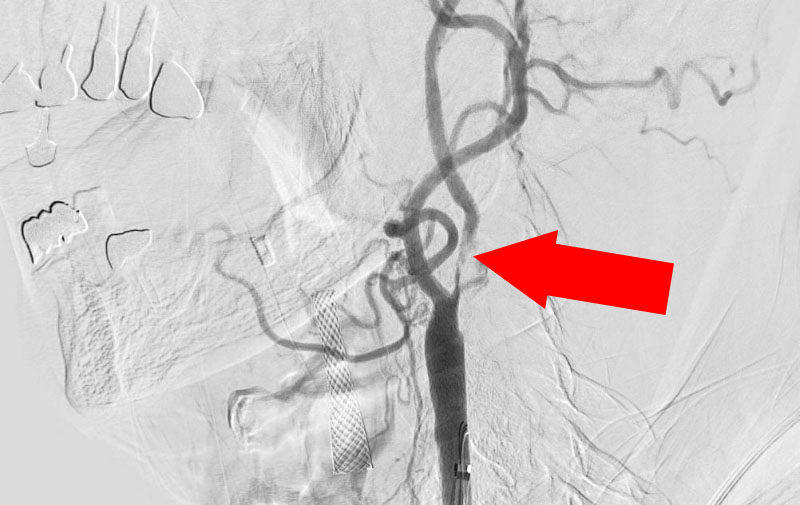

No.1203 手術中